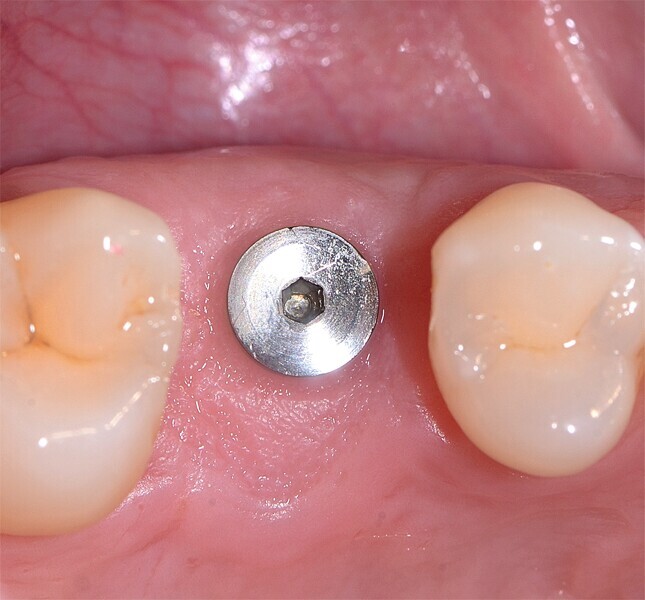

Fig. 38 : Pose de l’implant deux pièces en céramique au niveau tissulaire.

Fig. 39 : Pose de l’implant deux pièces en céramique au niveau tissulaire.

Fig. 40 : Pose de l’implant deux pièces en céramique au niveau tissulaire.

Un patient présentant un défaut infraosseux s’est présenté au cabinet dentaire avec le souhait explicite d’un traitement par un implant en zircone, pour remplacer l’une de ses molaires. Un implant deux pièces en zircone a donc été posé et le défaut infra-osseux a été traité dans le même temps, au moyen d’une allogreffe osseuse et du dérivé de matrice amélaire Emdogain (Straumann). La mise en charge n’a pas été réalisée à ce stade (Figs. 35–45).